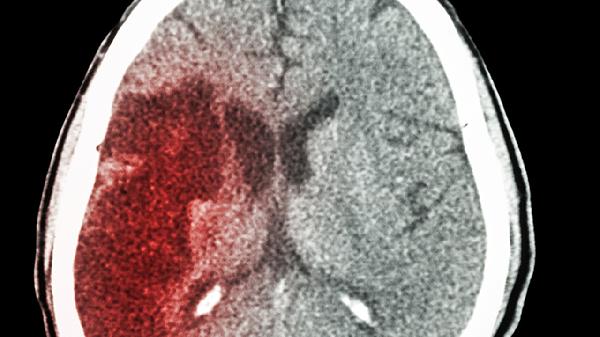

脑出血复发时间通常在1-5年内,具体与基础疾病控制、生活习惯等因素相关。复发风险较高的阶段集中在出血后1-2年,5年后复发概率会显著降低。

脑出血后1-2年内是复发的高危期。这一阶段血管壁损伤尚未完全修复,高血压、动脉硬化等基础病因若未得到有效控制,容易再次引发血管破裂。患者可能因情绪激动、剧烈活动或血压骤升导致二次出血。临床观察显示,约半数复发案例发生在此时间段内。严格控制血压在140/90毫米汞柱以下,定期进行脑血管评估,有助于降低风险。部分患者可能存在脑血管淀粉样变性或动脉瘤等隐匿病变,需通过磁共振血管成像进一步排查。